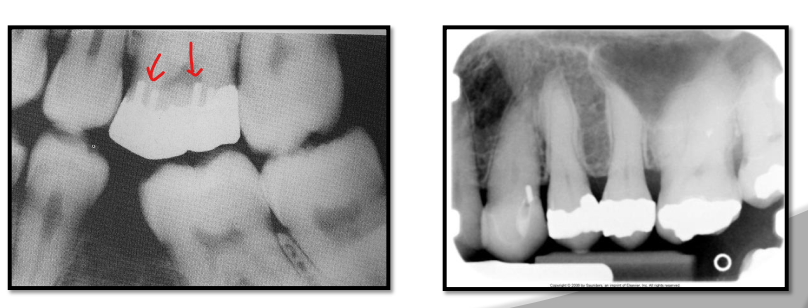

What class of interproximal caries is this?

Class 1 - incipient lesion

Class 2 - Moderate

Class 3 Advanced

Class 4 Severe